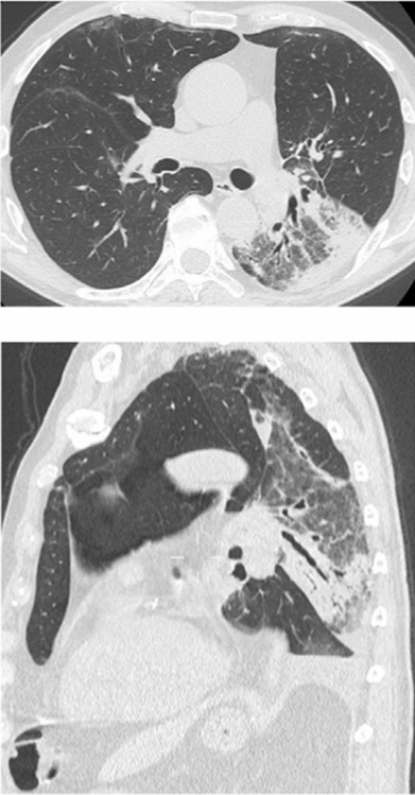

这“翻转”来的太突然,即使再次胸片检查也依旧如此。不得已行CT检查和三维渲染重建,见图3。胸部CT示右侧斜裂反转,中间支气管异常前行,肺血管旋转;右下肺动脉与中间支气管一起被拉向前行;右肺广泛实变,并伴有胸腔积液;外观显示右肺发生了180度扭转。

图3 胸部CT